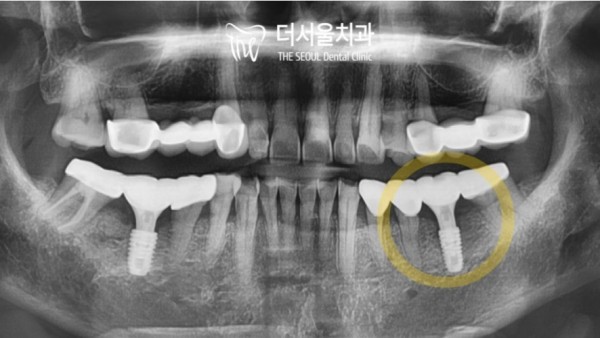

신경관과의 거리에 주의해서

게획했던 그대로 픽스처를 안전하게 심었습니다.

잘 보시면 골이식도 함께 진행된것을 확인할 수 있답니다.

이후에는 몇개월 정도의 시간이 필요합니다.

픽스처가 단단히 고정될 시간이 필요하기 때문입니다.

Paying attention to the distance from the nerve tube

I planted the fixture safely as planned.

If you look closely, you can see that bone grafts have also progressed.

After that, we need a few months.

This is because the fixture needs time to be firmly secured.

그리고 시간이 흘러 단단하게 픽스처가 고정되었을때

이렇게 크라운을 올려서 임플란트를 마무리할 수 있게되었습니다.

예전 빈공간이 있던 자리에는 크라운이 잘 올라가 있는것을 알 수 있습니다.

And over time, when the fixture is firmly fixed

The implant can be finished by raising the crown like this.

You can see that the crown is well placed in the former empty space.